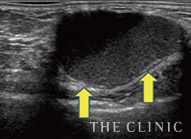

脂肪注入豊胸後に生じたしこりと除去の様子(エコー画像)

-

施術前

吸引中

施術後